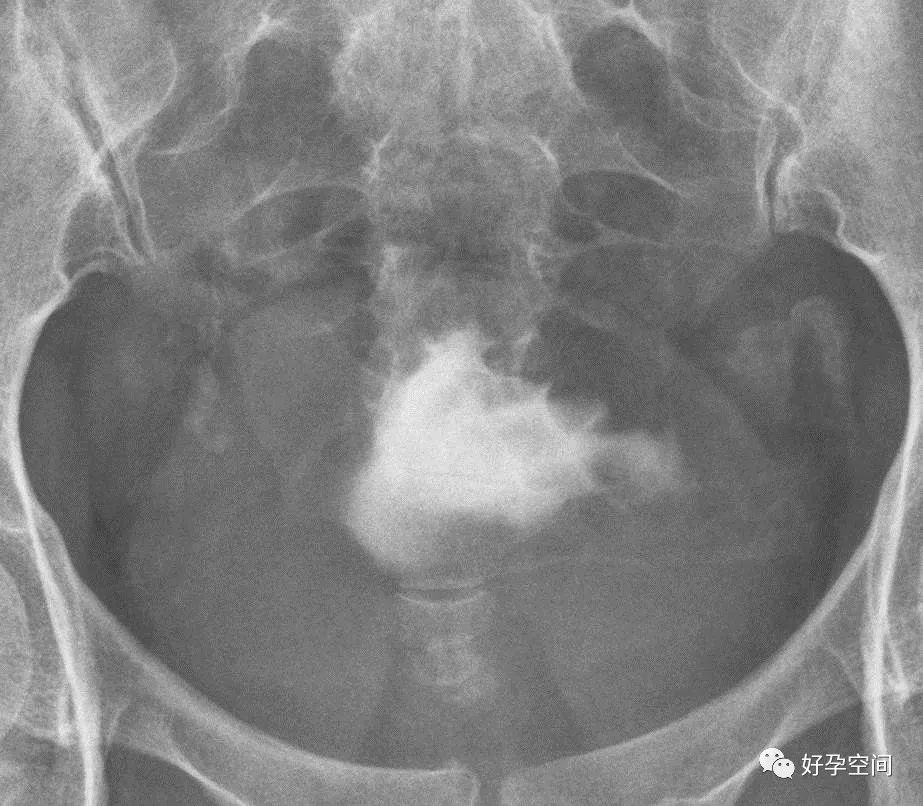

输卵管相